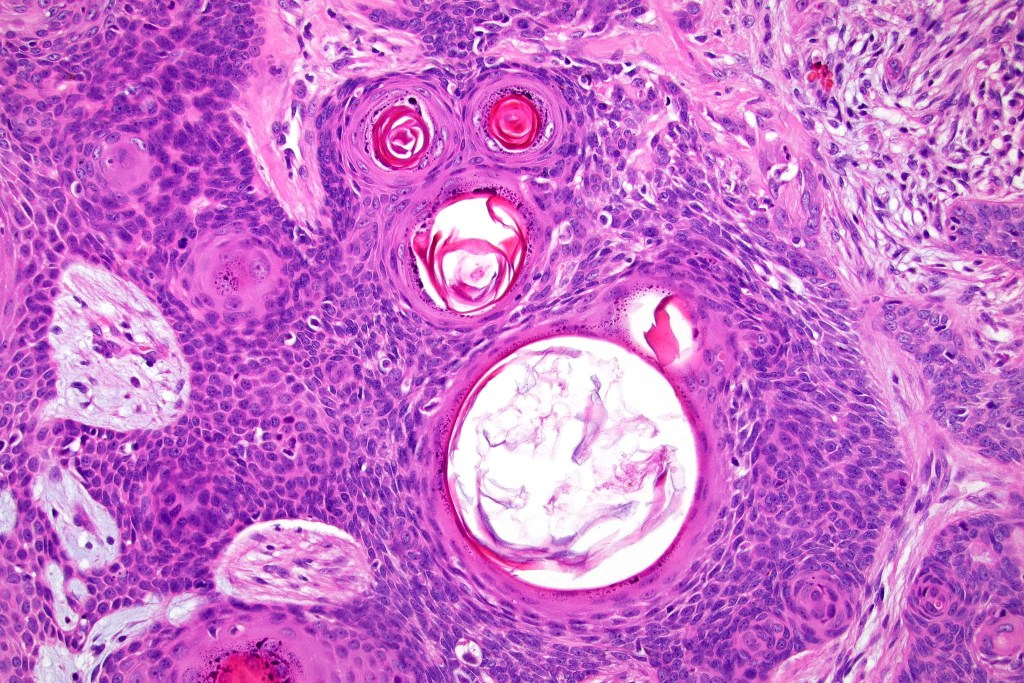

•Variable keratocysts

•A rich fibromyxoid mesenchymal stroma with variable papillary mesenchymal bodies (sometimes these are absent)

•Trichogerminoma is a distinctive variant being composed of tumor nodules with basaloid cells surrounding pale or eosinophilic micronodules (Zellballen)